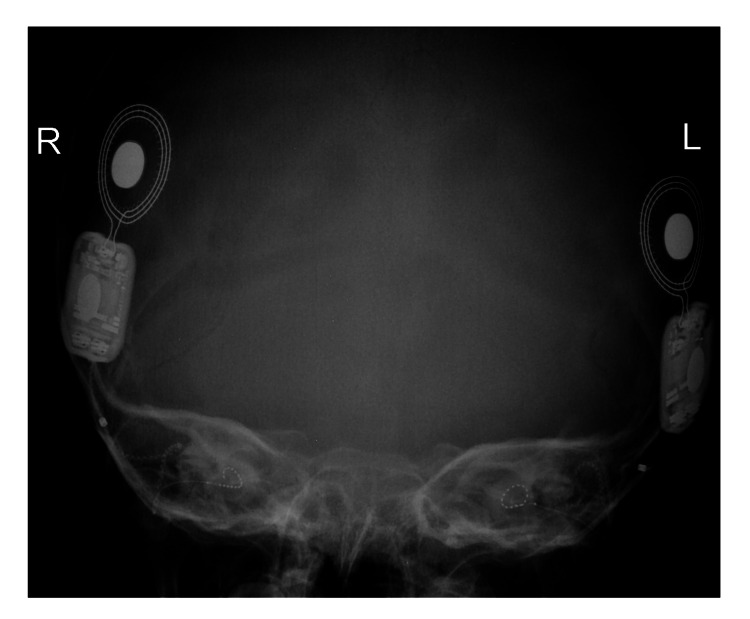

患者被 CI 委員會確定為雙側(cè)植入的候選者。 在三歲零五個月大時,進行了雙側(cè)同時人工耳蝸植入(HiRes™ Ultra #D 人工耳蝸,右 HiFocus™ SlimJ 電極和左 HiFocus™ Mid-Scala 電極,Advanced Bionics AG,加利福尼亞州,美國)。 術(shù)后 X 線顯示 CI 陣列有效插入耳蝸內(nèi)(圖 2)。 手術(shù)后第二天開機,并給予兩個 Naida CI Q70 聲音處理器(Advanced Bionics AG,加利福尼亞州,美國)。

An external file that holds a picture, illustration, etc.

Object name is cureus-0014-00000021063-i02.jpg

病例 2 的術(shù)后 X 線顳骨顯示雙耳人工耳蝸電極陣列有效插入